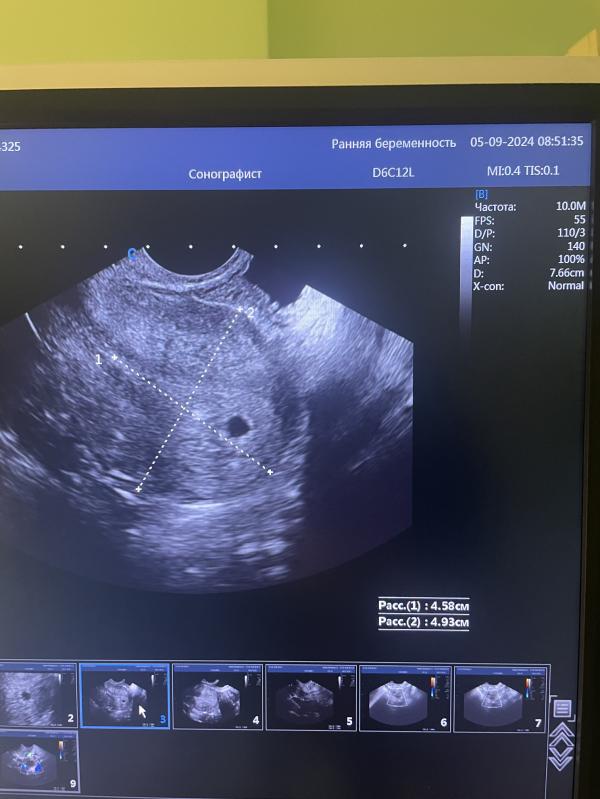

УЗИ 5,1 неделя

ПЯ 5,1 мм

ЖМ 1,8 мм

ЖТ 24мм

Эндометрий 13мм

05.09.2024